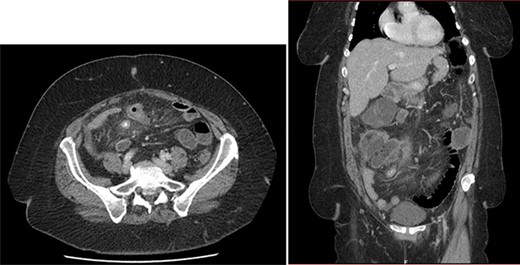

First, we embolized the splenic artery with coils (Fig. 3). The patient was getting well at intensive unit care, but few hours after embolization, she was shocked again.